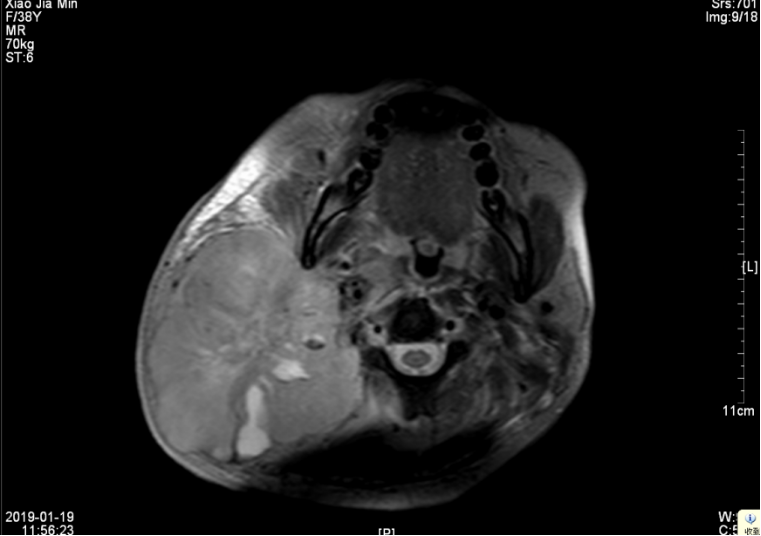

查【EB病毒五项】EB病毒VCA抗体(IgA) 阳性(+),EB病毒壳抗原(VCA)IgG抗体 阳性(+),EB病毒核抗原(EBNA1)IgG抗体 阳性(+),EB病毒早期抗原(EA)IgG抗体 阳性(+)。【肿瘤筛查1组(女)】糖链抗原CA-153 45.3U/ml。恶性肿瘤特异性生长因子 77U/ml。鼻咽MRI:1、考虑鼻咽癌,并侵犯周围结构及颅底骨质,伴右侧颈部、咽旁淋巴结多发转移(最大约60mm×49mm),请结合临床及其他检查。2、副鼻窦炎,右侧中耳乳突炎(见图一、二)。

▲图一 2019年1月19日 治疗前淋巴结MRI(60mm×49mm)

▲图二 2019年1月19日 治疗前鼻咽部肿块MRI